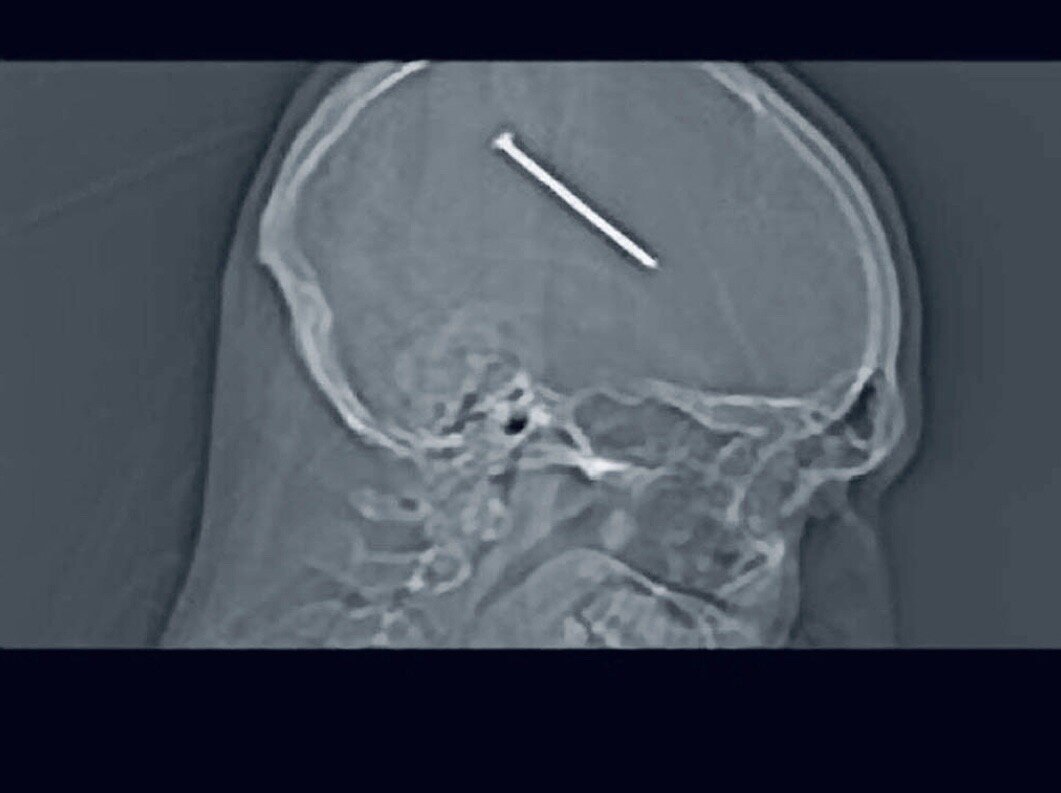

Когда он пришёл к врачу, то ему сразу назначили томографию, и когда были готовы снимки, люди не поверили своим глазам. В голове мужчины был гвоздь размером около восьми сантиметров. При этом, он ходил и чувствовал себя не плохо, за исключением тошноты.

Как оказалось, гвоздь не задел ни один нерв в мозге, и поэтому мужчина был в нормальном состоянии. Это невероятно, но даже врачи сказали, что это настоящее чудо, ведь если бы гвоздь сдвинулся хотя-бы на пару миллиметров, то состояние было бы плачевно.